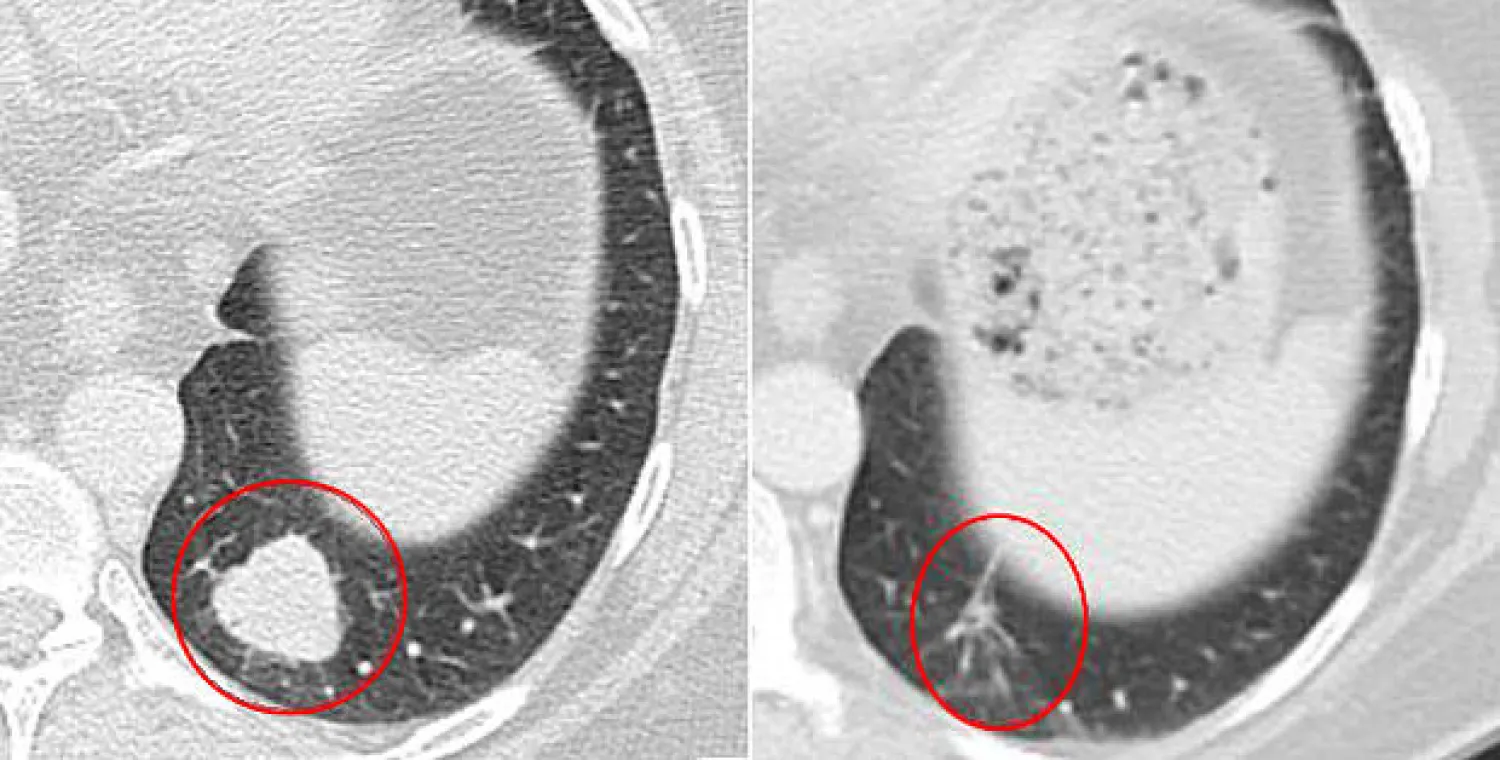

كانت هذه نتائج اختبارات لعدد من العلاجات التي تقيّد النظام المناعي بالجسم، وتم إعلانها خلال المؤتمر السنوي لجمعية طب الأورام في شيكاغو مساء أمس (الأحد). وجاءت النتائج مبشّرة في مكافحة سرطان الجلد ومرض الرئة.

وتقول صحيفة «تلغراف» البريطانية، إن النتائج أظهرت تأثيرا «مذهلا» ضد الكثير من أنواع السرطان، فيما قال خبراء إن المرضى في المراحل المتقدمة من الإصابة بالسرطان، بما فيها سرطان الرئة والمعدة والمبيض والرحم، قد يتم علاجهم بالعقاقير في المستقبل.